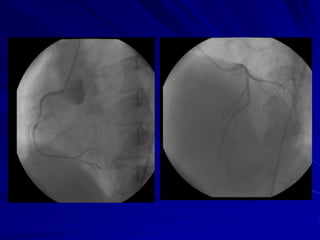

Coronary angiogram

Interventional treatment

PTCA (Ballooning) Stenting